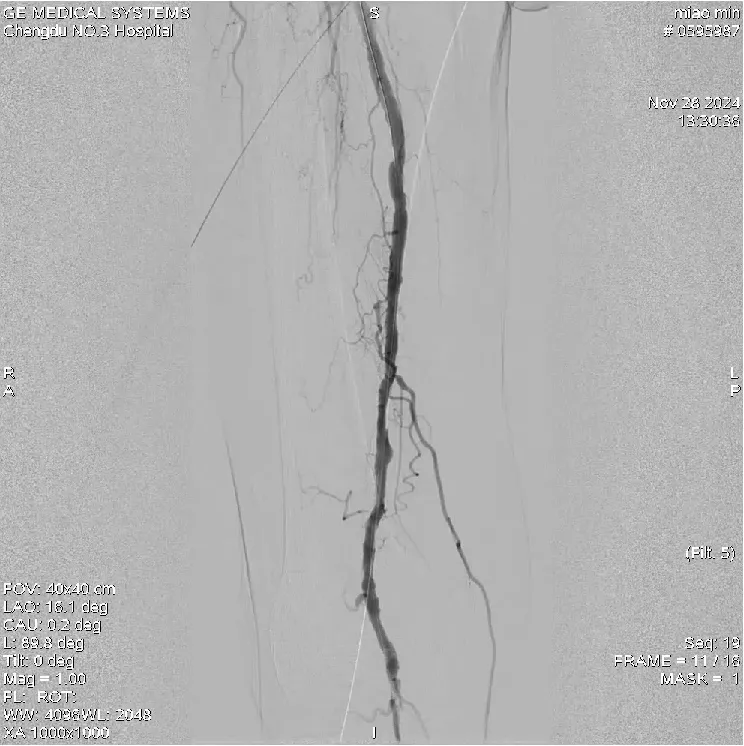

1、術前造影示:右側股淺動脈中下段及腘動脈多發狹窄合并短段閉塞,膝下脛前動脈閉塞,腓動脈及脛后動脈血流通暢;

5、術后造影示:血流通暢,病變解除;